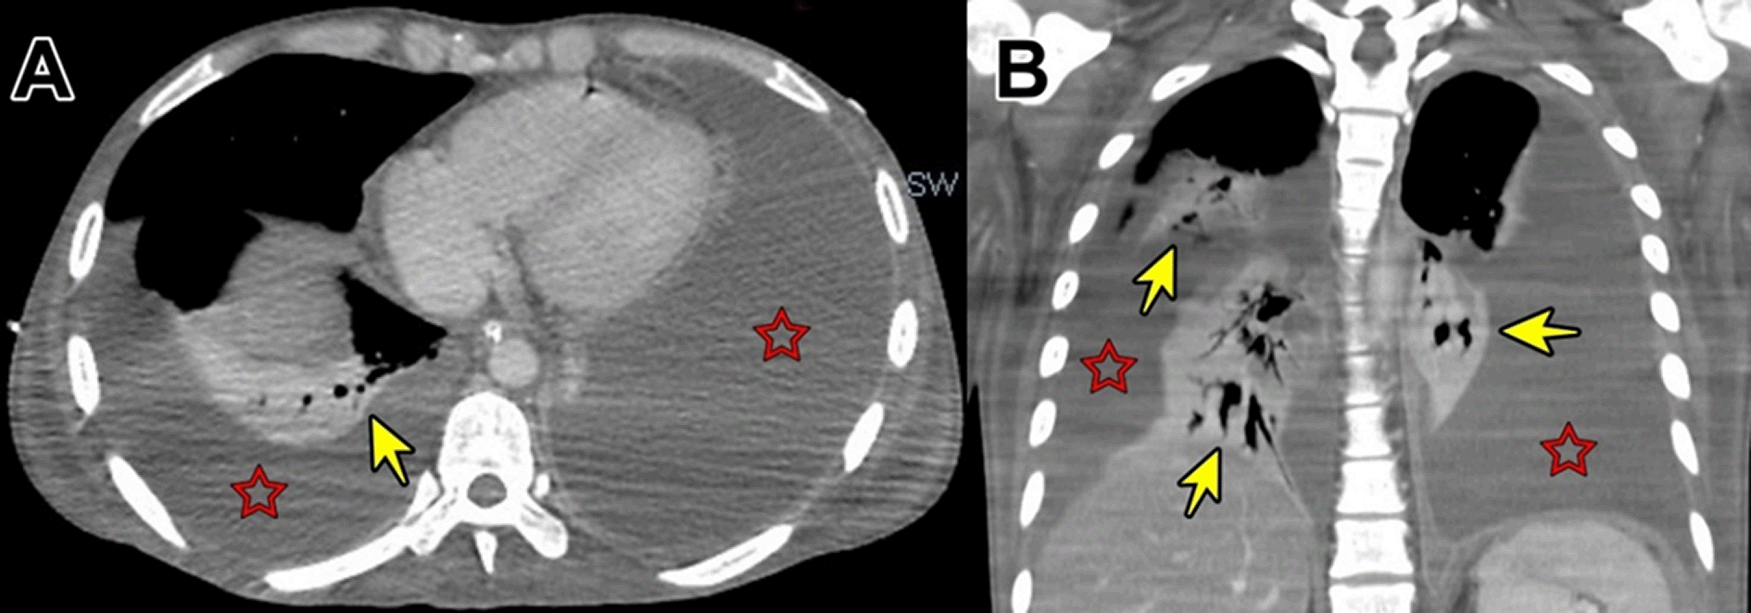

Evolution. After admission, acute abdomen due to appendicitis was diagnosed. Symptomatic treatment was initiated and preoperative exams and plain chest and abdominal x-ray were ordered, which showed significant bilateral pleural effusion and ascites. Three hours after admission, the patient was transferred to the operating room. During exploratory laparotomy “multiple cerebroid nodules scattered through parietal and visceral peritoneum, small bowel, colon and epiploon; and plenty of ascitic fluid were observed”. The postoperative diagnosis was “carcinomatosis”. After surgery, he was transferred to the ICU, and continued treatment with saline, noradrenaline, imipenem, metronidazole, sedation with midazolam, analgesia with fentanyl, and ventilatory support. Based on clinical data, risk factors, intraoperative findings, and chest x ray imaging, TB was suspected. Then, stains and cultures of multiple samples for Mycobacterium tuberculosis (MTB) and a contrast-enhanced tomographic scan of thorax, abdomen and pelvis were ordered (Figure 5). Three days after surgery thoracocentesis was performed. Five days after surgery RT-PCR resulted positive for MTB in pleural fluid and quadruple anti-tuberculous treatment for MTB was initiated (the same scheme as Case 1). Ten days after surgery histopathology of epiploon was obtained, showing extensive caseous necrosis with granulomas and Langhans multinucleated giant cells. The patient died seven days after initiation of anti-tuberculous treatment due to refractory septic shock (Figure 6). A serial ZN smear for AFB in bronchial secretion, blood cultures, and urine culture, were negative. Serologies for HIV, HTLV-1, hepatitis B and C, and RPR/VDRL, were also negative.